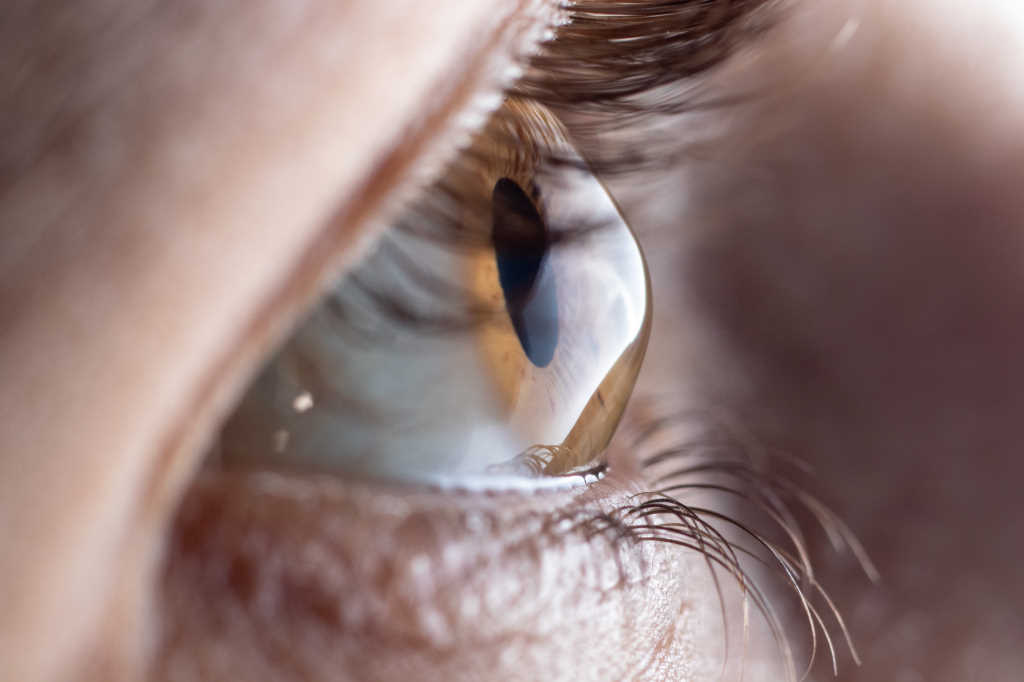

Keratoconus appears both more common and more severe in Aotearoa than in many other countries and it has been the most common indication for corneal transplantation in New Zealand for several decades. Collagen corneal cross-linking (CXL) provides the opportunity to halt or slow the progression of keratoconus and has been available in Auckland since 2007.